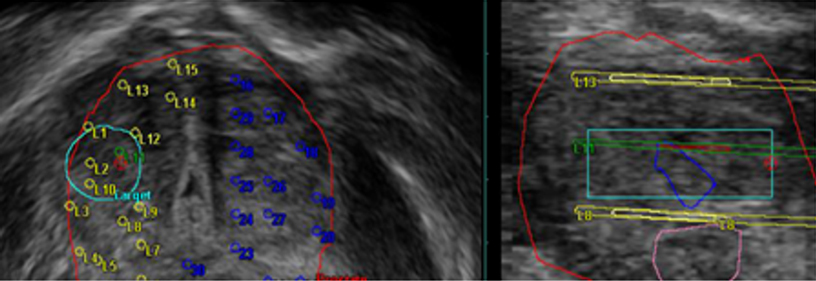

Brachytherapy – compatible with common Focal Treatment planning software

Cryotherapy zones: display of temperature distribution curves*1